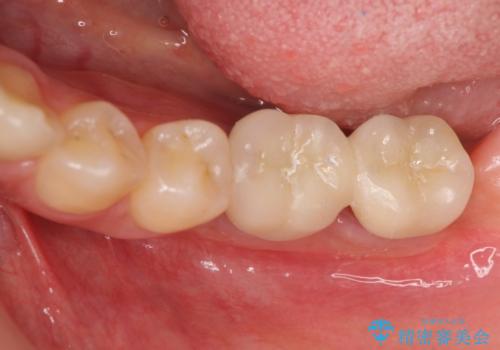

臼歯の噛み合わせをインプラントを用いて回復する

- 他院で抜歯後放置してしまった左下の奥歯の機能・見た目の回復を希望され来院されました。

インプラントを用いて機能回復を行うことで、奥歯がしっかりと噛めるようになります。